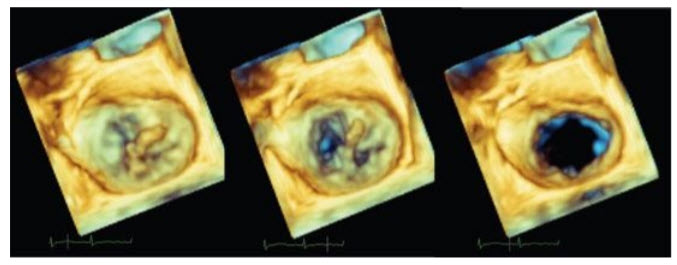

A TEE is performed urgently (Fig. below) shows a 3D view of the mitral valve from above).

What is the most likely diagnosis?

Posterior papillary muscle rupture as it has a single blood supply. The 3D reconstruction of the mitral valve shown here is orientated in the “surgeons view,” looking down on the mitral valve from the left atrium with the aortic valve situated on top, the anterior mitral valve leaflet adjacent to it, and the posterior mitral valve leaflet inferiorly. We see a bulky mass (the posterior papillary muscle) protruding into the left atrium in systole. The middle panel (early diastole) clearly shows that the mass is attached to the posterior leaflet. The posterior papillary muscle has a single blood supply (usually the right coronary artery), while the anterior papillary muscle often has dual blood supply. For this reason, post infarction rupture of the posterior papillary muscle is more common.